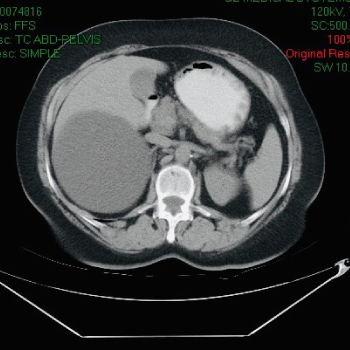

Quistes en el Hígado

Los quistes en el hígado son los tumores benignos muy frecuentes. Son bolsitas con agua que salen dentro del hígado. La mayor parte de las veces no producen ningún problema, pero en otras ocasiones los quistes en el hígado pueden ser por cáncer, Infecciones o estar producidos por parásitos.